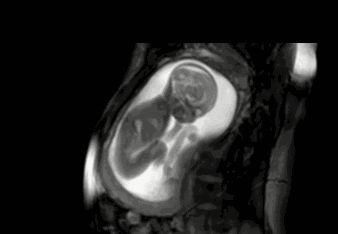

大部分胎儿在怀孕16周的时候其实就开始运动了,不过这个时候由于他的运动幅度比较小,所以孕妈们可能感受不到。

比较明显的胎动在孕期32周,这个时候宝宝的一举一动更有力量,体现在胎动上也就更加明显。所谓胎动实际上就是胎儿在子宫里活动并碰到子宫壁。它代表胎儿的活力,从侧面证明了发育的情况。

胎动太频繁或者长时间都不胎动,很有可能就是胎儿出现了问题。而规律的胎动代表着胎儿发育良好且比较聪明。

如果胎动能达到每两个小时6-10次胎动,就说明胎动很规律。2、孕妈情绪稳定